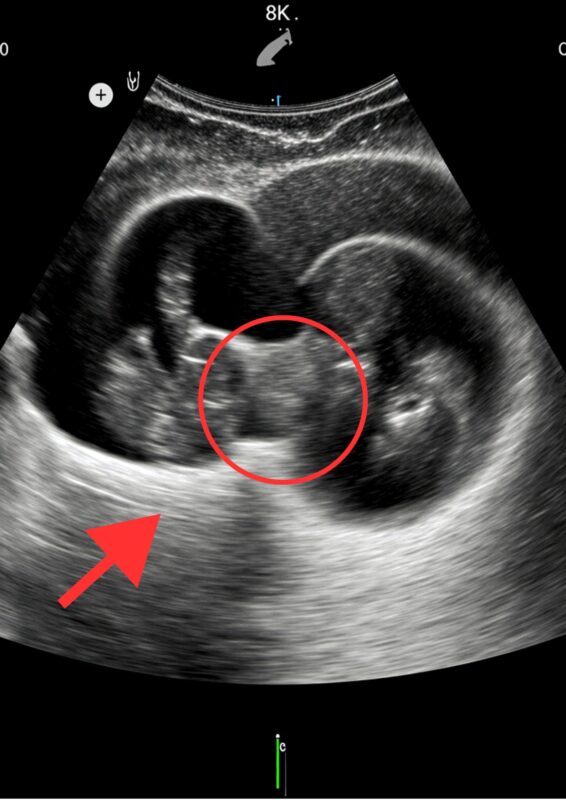

“Here are two heads… two babies… they’re lying face to face… but wait— they’re not hugging. They’re connected.”

Julia froze. Her smile disappeared as the doctor explained that the babies were conjoined at the abdomen, sharing a small part of their liver and the abdominal wall. Though they were developing normally, this tiny fusion could become a huge problem later.